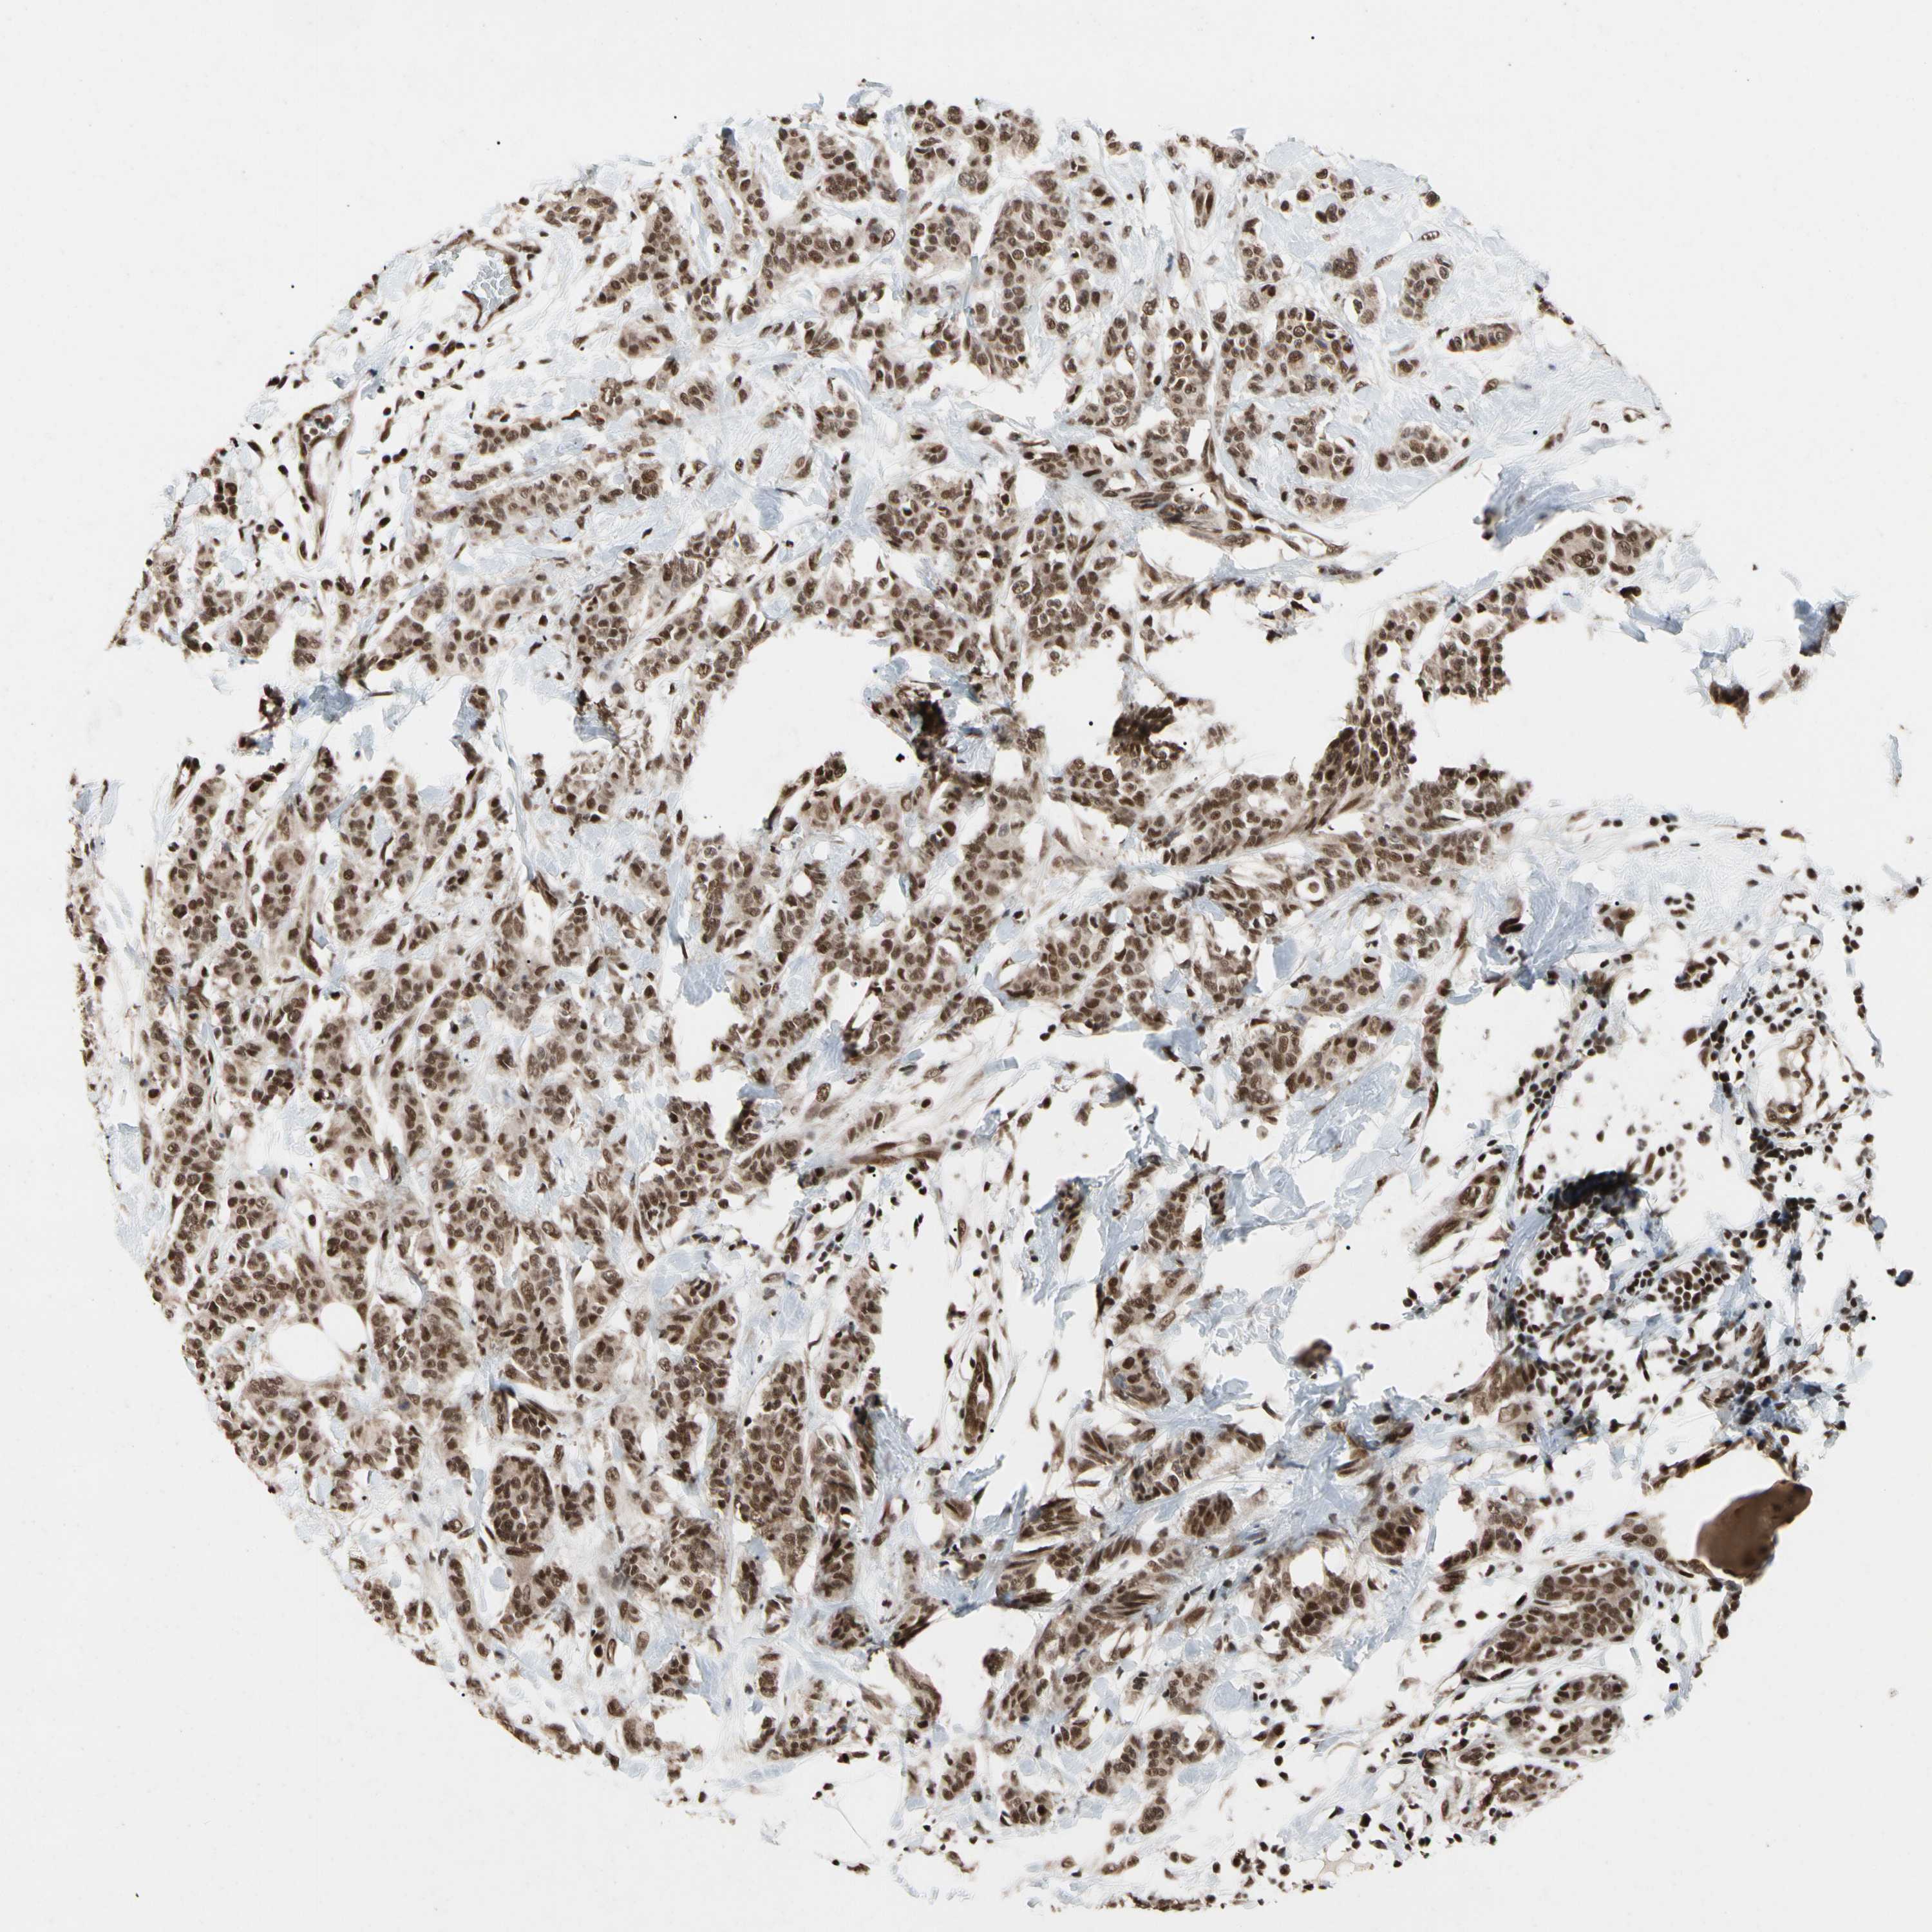

BRCA TCGA BRCA VALIDATION PROTEIN EXPRESSION

Breast cancer

Human cancer

FAM98B is potential prognostic, high expression is unfavorable in Breast Invasive Carcinoma (TCGA)